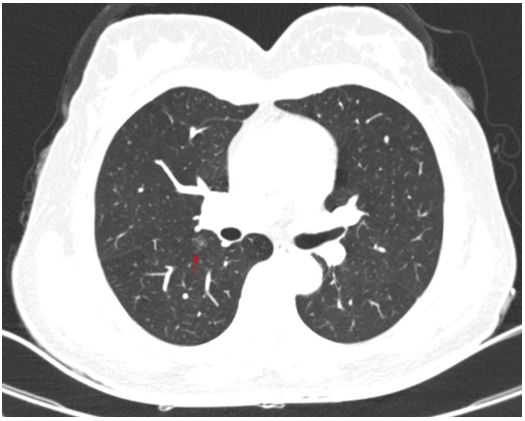

原标题:【医疗】三维重建助力胸外科完成多例精准肺段切除术 患者术前胸部CT检查结果,箭头所指处为病灶,表现为磨玻璃样结节 45岁患者王女士家住丹东市,体检时发现右肺下叶磨玻璃密度小结节,影像学上符合早期肺癌的表现,王女士及家人非常焦虑,四处求医。医生给王女士的建议都是手术切除。王女士肺部的病灶虽然体积较小,直径约1cm,但由于病变靠近肺门深处,采用常规的肺楔形切除手术非常困难,甚至可能对肺组织造成较大的损伤。如果行肺叶切除,王女士又担心术后肺功能的损失较多,恐怕术后不能从事繁重工作。王女士接受手术治疗的意见,但是她希望手术的效果是即能切除病灶,又可以最大限度的保留正常肺组织。经地方医院介绍,王女士来到我院第二胸外科病房找到了石文君主任。 入院后,王女士进行了胸部增强CT+三维重建的检查,随后进行了支气管血管三维重建,根据三维重建的结果,石主任带领团队为王女士制定了精准肺段切除的手术方案。由于术前已经从三维重建图像中得知了血管及支气管的变异,手术进行的非常顺利,手术时间及出血量均较常规的肺叶切除手术无明显差别,术后王女士恢复顺利并出院。现王女士术后已有半年,来复查时欣喜地告诉我们,目前她仍可以从事之前较为繁重的工作,体力上也相当充沛。目前类似于王女士这种情况的患者非常多,第二胸外科病房现已完成多例胸腔镜下精准肺段切除术,帮助患者获益。 三维重建立体图像,白色为支气管,红色为动脉,蓝色为静脉,黄色为病灶所在位置 支气管及肺动静脉3D打印模型 胸腔镜肺段切除术是早期肺癌的重要治疗手段之一,精准的手术是肿瘤学疗效和肺功能保护的前提。精准肺段切除术的目标是在彻底切除病灶的同时最大程度地保留健康肺组织。但是精准肺段切除最大的难点在于每个人解剖的不确定性,因为肺血管、支气管细枝末节就像一棵树,每个人长得都不一样。要做到精准切除,首先就要确定病变在哪一个肺段,其次需要精确判断该肺段的动脉、静脉、支气管有没有畸形,需要切断哪一个,保留哪一支。这些信息都需要三维重建图像提供给我们,所以说“无重建,不精准”。 目前高龄患者及肺小结节的患者很多,精准肺段切除非常适合这类肺小结节或无法耐受肺叶切除的高龄患者的治疗。开展精准肺段切除的最大难点准确分辨肺段的静脉、动脉、支气管及段间平面,有3D-CTBA重建影像指导的肺段切除术才是精准肺段切除术。我院第二胸外科病房将三维重建及3D打印技术应用到肺段切除术前,做到“精准”肺段切除。术前对拟行肺段、肺亚段切除病例行薄层CTA检查,获得DICOM影像资料在计算机上使用软件进行三维重建,生成立体图像在三维图像上进行测量,提前发现患者存在的解剖变异,规划手术区域及手术径路,设计手术方案,选定需要切断的靶血管及支气管和需要保留的血管及支气管,设计段间切割线胸腔镜手术,根据术前的规划完成手术。因术前进行了准确的三维重建,可以在手术开始前及时发现解剖变异,在术中准确辨认所需切除术的血管及支气管,防止误断,提高了手术的精确性及安全性避免了因复杂的肺段解剖而带来的问题。 在日前由我院第二胸外科病房举办的“2019盛京医院胸外论坛暨盛京第一届精准肺段研讨沙龙”上,石文君主任主持大会。北京大学人民医院李剑锋教授等多名国内胸外科专家应邀参会并作了“近红外荧光显像在肺段切除中的应用探索”等专题报告,还进行了单操作孔胸腔镜下左肺下叶前基底段切除的手术演示。 在石文君主任的带领下,第二胸外科病房除了常规开展胸腔镜肺癌根治术、食管癌根治术、纵隔肿瘤切除术外,目前已成熟掌握并开展精准肺段切除术。但是对于临床分期不同的肺癌,其治疗效果差异较大,只有早期肺癌才有接受“精准肺段切除”治疗的机会,其手术创伤小,能彻底切除目标病灶,最大限度减免肺组织损伤,确保剩余肺结构完整和功能代偿。因此在肺癌的治疗中,早期发现尤为重要,建议特别是45岁以上、有吸烟史、家族遗传倾向的高危人群,应每年进行一次胸部CT检查;对于上述高危因素的人群,也应适时进行体检,争取做到早期发现及治疗。